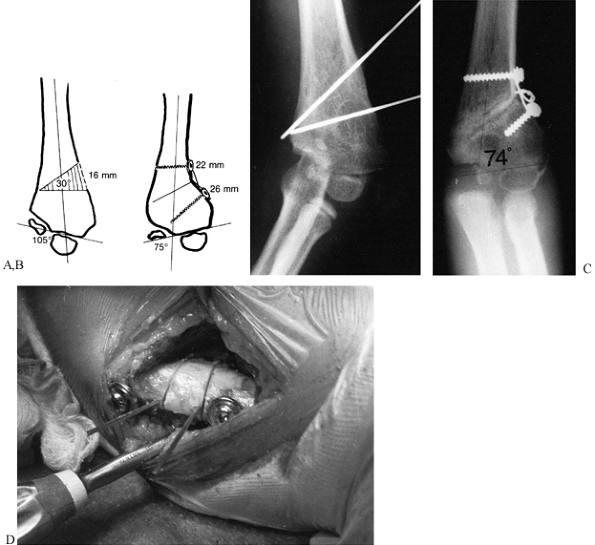

patient is standing perfectly erect. Comparison of all these